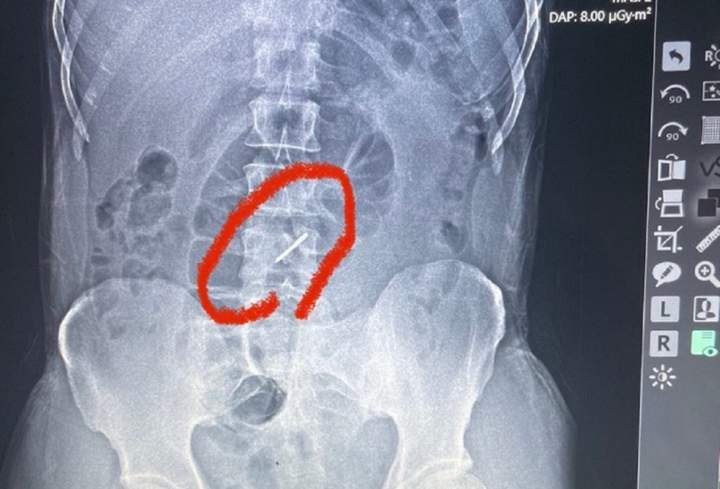

Як розповів лікар військово-польового госпіталю Тарас Кобза, коли бійця скерували на рентген, аби чітко встановити причину болю, то лікарі були шоковані побаченим на рентгенівському знімку.

"Під час обстрілу елемент касетної бомби, так звана "стрілка", потрапила у ліве підребер'я, зламала два хребці у поперековому відділі хребта і застрягла у хребті. Уламки зламаних хребців могли ушкодити нерви, судини, але, на щастя, цього не сталося. Боєць прийшов у польовий госпіталь своїми ногами і навіть не підозрював, що у його хребті застряг елемент касетної бомби", – каже Тарас Кобза.

За його словами, боєць потрапив під обстріл ще 13 липня, а до шпиталю звернувся лише на початку серпня. Він практично три тижні воював зі зламаним хребтом. Наразі бійця із зони бойових дій відправили в одну з лікарень у більш безпечний регіон, де він проходитиме лікування.